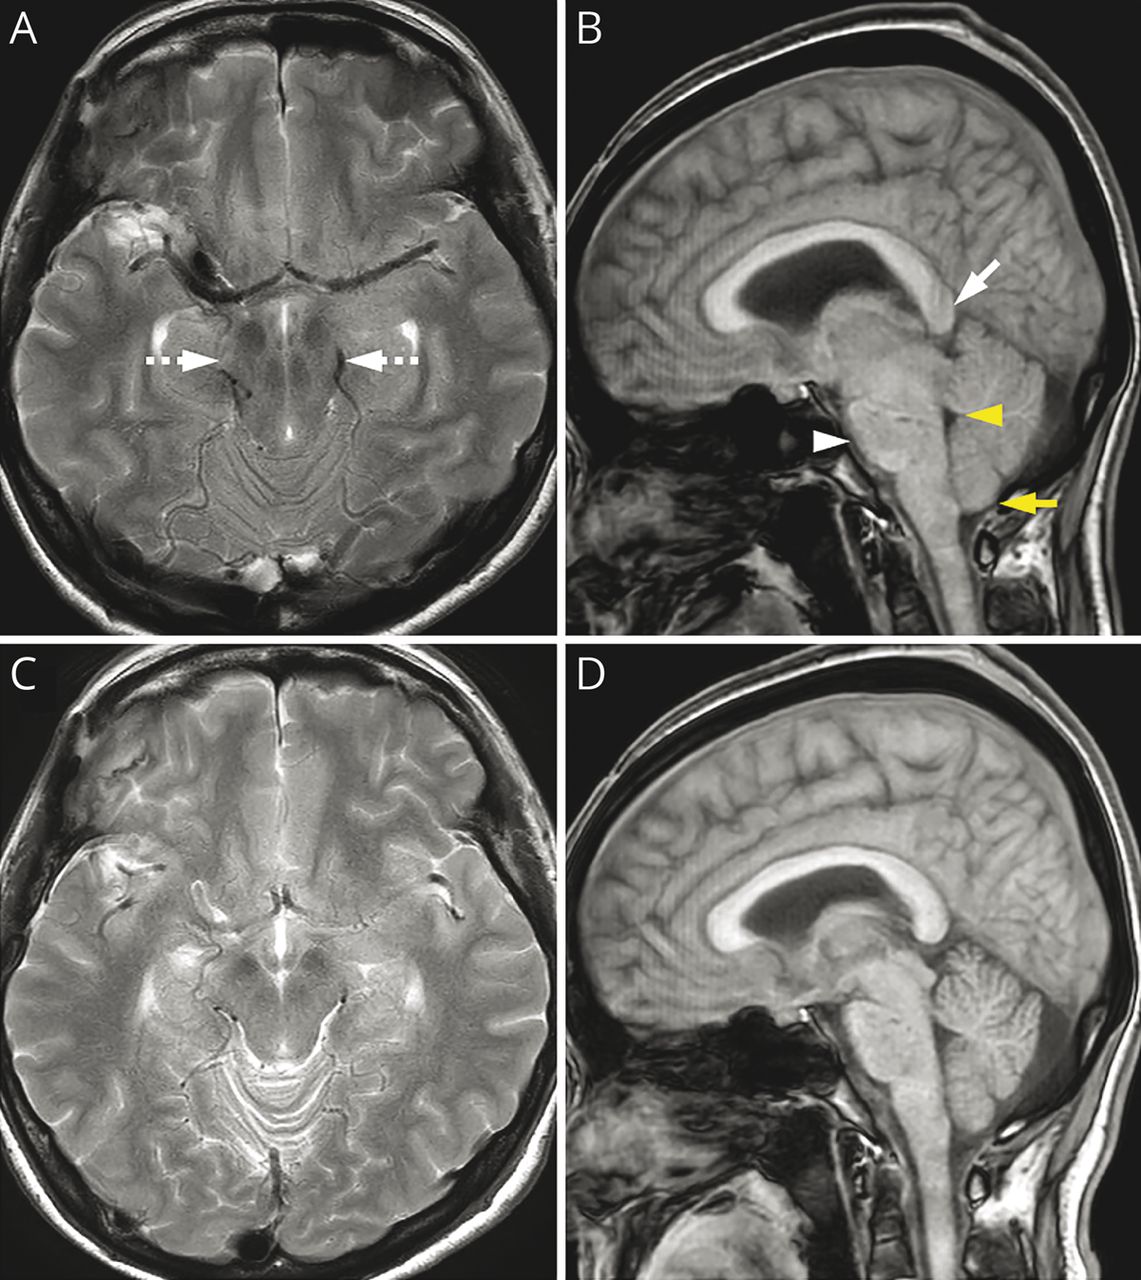

初始轴向t2加权成像(A)和矢状位t1加权成像(B)显示明显的中脑压迫(虚线箭头)、脑干下垂(箭头)、脾下下垂(箭头)、第四脑室狭窄(黄色箭头)和小脑扁桃体突出(黄色箭头)。(C, D)分流压力调整后,脑干周围结构恢复。

患者,51岁,女性,在蛛网膜下腔出血后腰腹腔分流术治疗脑积水6个月后,出现眼睑张开失用症,随后出现缓慢进展的掩相、舌颤、吞咽困难、颈部及上肢僵硬、运动迟缓。脑部MRI检查显示中脑受压,脑干下方移位,脑池淤积,与幕下低血压一致。123i -氟烷SPECT成像显示双侧纹状体多巴胺转运蛋白结合减少。增加分流压力后,所有症状和表现均有所改善(图1和图2和视频1).UPDRS第三部分得分从24分提高到5分。颅内低血压伴中脑下垂可引起可逆性帕金森病1,2当位移剪切力损害黑质纹状体多巴胺通路。